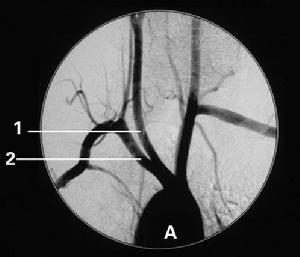

(1)CT掃描:可顯示腦皮質和腦白質內多發的大小不等低密度梗死灶,側腦室體旁暈狀低密度區腦白質疏鬆症(leukoaraeosis)和腦萎縮等。

CT:腦梗死灶位於基底節區31例,丘腦7例,額顳枕葉8例,梗死灶12例,2個以上44例,廣泛性腦萎縮33例,局限性腦萎縮13例,腦室擴大伴腦萎縮42例。

腦梗死大小、部位與痴呆:過去,進行性腦功能衰退所致的痴呆被人認為是腦動脈硬化所致的腦缺血、缺氧引起,但近年來臨床研究已明確,真正的腦血管痴呆是由於多次發作的腦梗死所致的腦組織累積性損害,故亦稱多梗死性痴呆(MID),病理檢查已證實MID患者有足夠的腦組織損害才能產生痴呆,多數人認為梗死灶體積與痴呆的嚴重程度有密切關係,梗死灶體積越大越容易引起痴呆。梗死灶容積>50ml可以合併痴呆,>100ml則經常合併痴呆。而本組結果大面積腦梗死占17.4%,小梗死灶占82.6%,多發病灶占95.6%,提示病灶體積小也可以發生痴呆,尤其是梗死數目越多,痴呆發生率會越高,所以雙側、多發病灶、皮層病灶、體積大的病灶與痴呆關係密切。其次我們認為MID基底節區發生率高(67.4%)是由於基底節區梗死多屬於分水嶺腦梗死,梗死部位主要是頸內動脈系統及深穿支小動脈終末供應區,側支循環差。當高血壓、腦動脈硬化等腦血管病變時,使動脈壁彈性減退,動脈內膜粥樣斑塊形成,造成管腔狹窄以至閉塞,導致多發性小灶梗死發生。此部位病變導致痴呆的原因可能為:基底節處核與核之間,各核與皮層之間有廣泛的纖維聯繫,許多纖維與記憶和認識功能有關,如受破壞即可出現痴呆,特別是主側半球腦的損害可導致痴呆。從而表明腦梗死部位、大小、範圍與痴呆有密切關係。